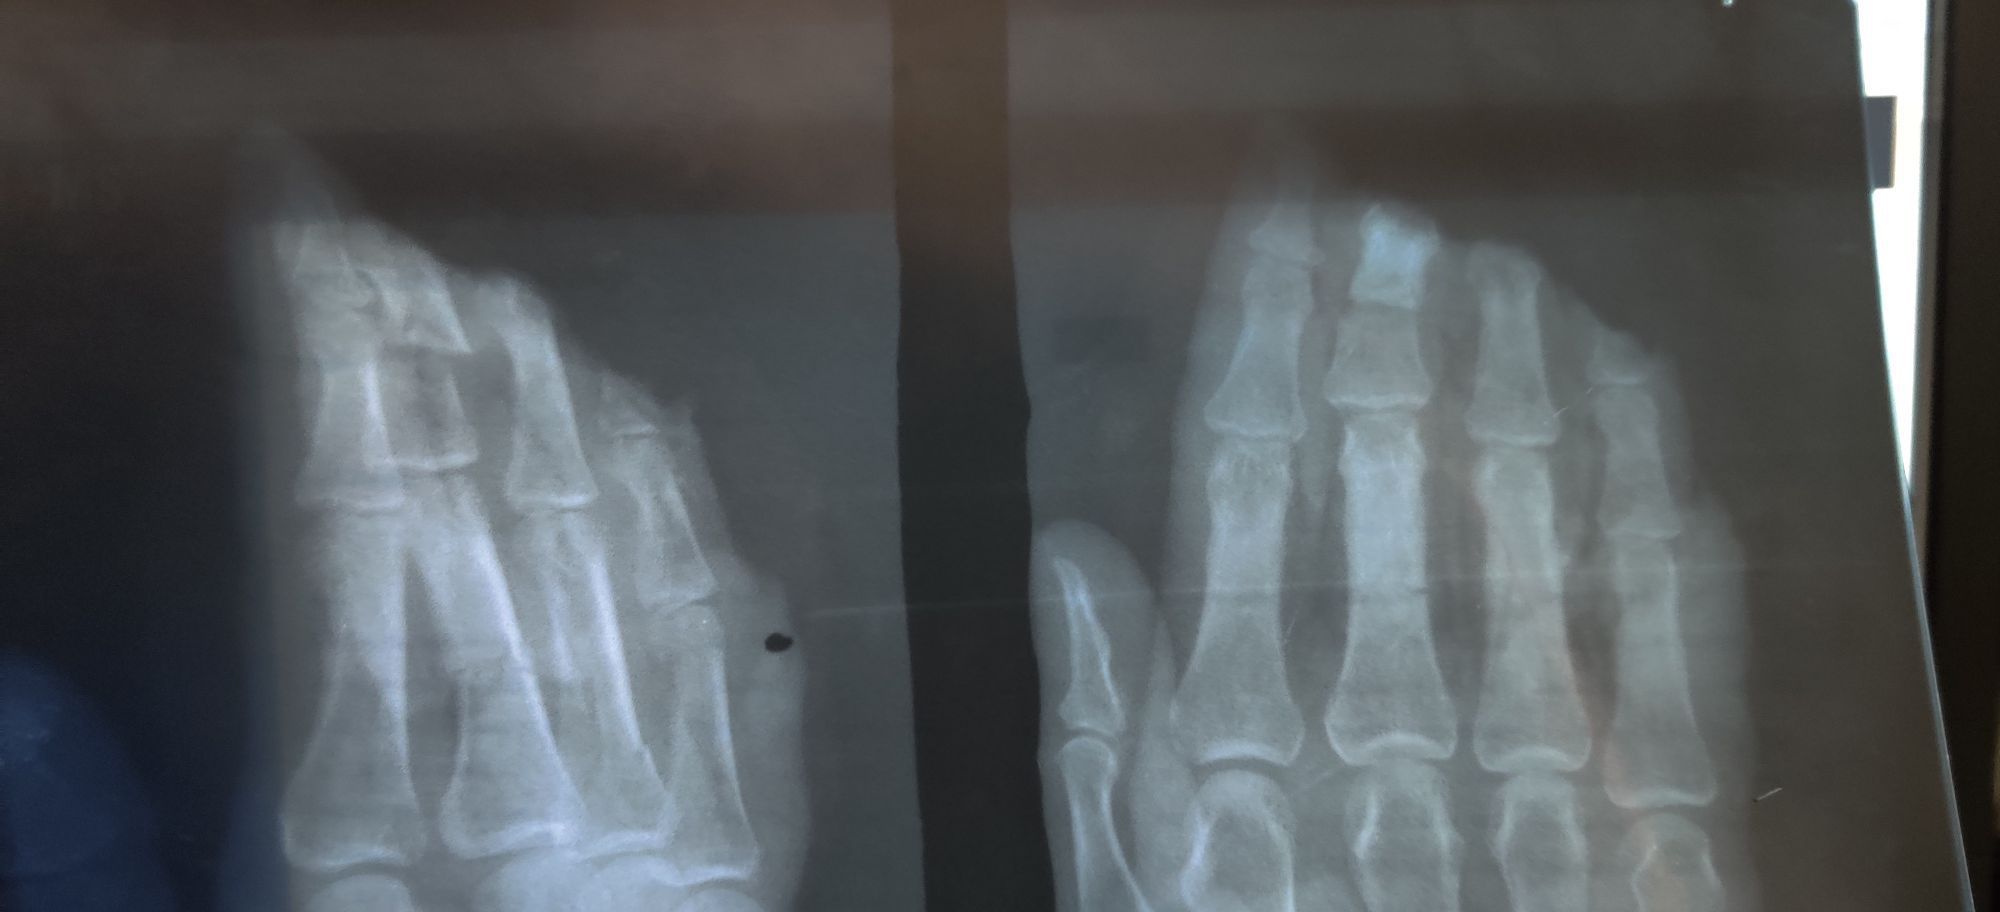

Traumatic Amputation

Trauma

Xray

Rta